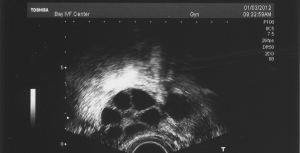

- Doctor visits and monitoring (ultrasounds, blood tests).

- Egg retrieval (a quick surgery to grab the eggs).

- Embryo transfer (placing the embryo in the uterus).